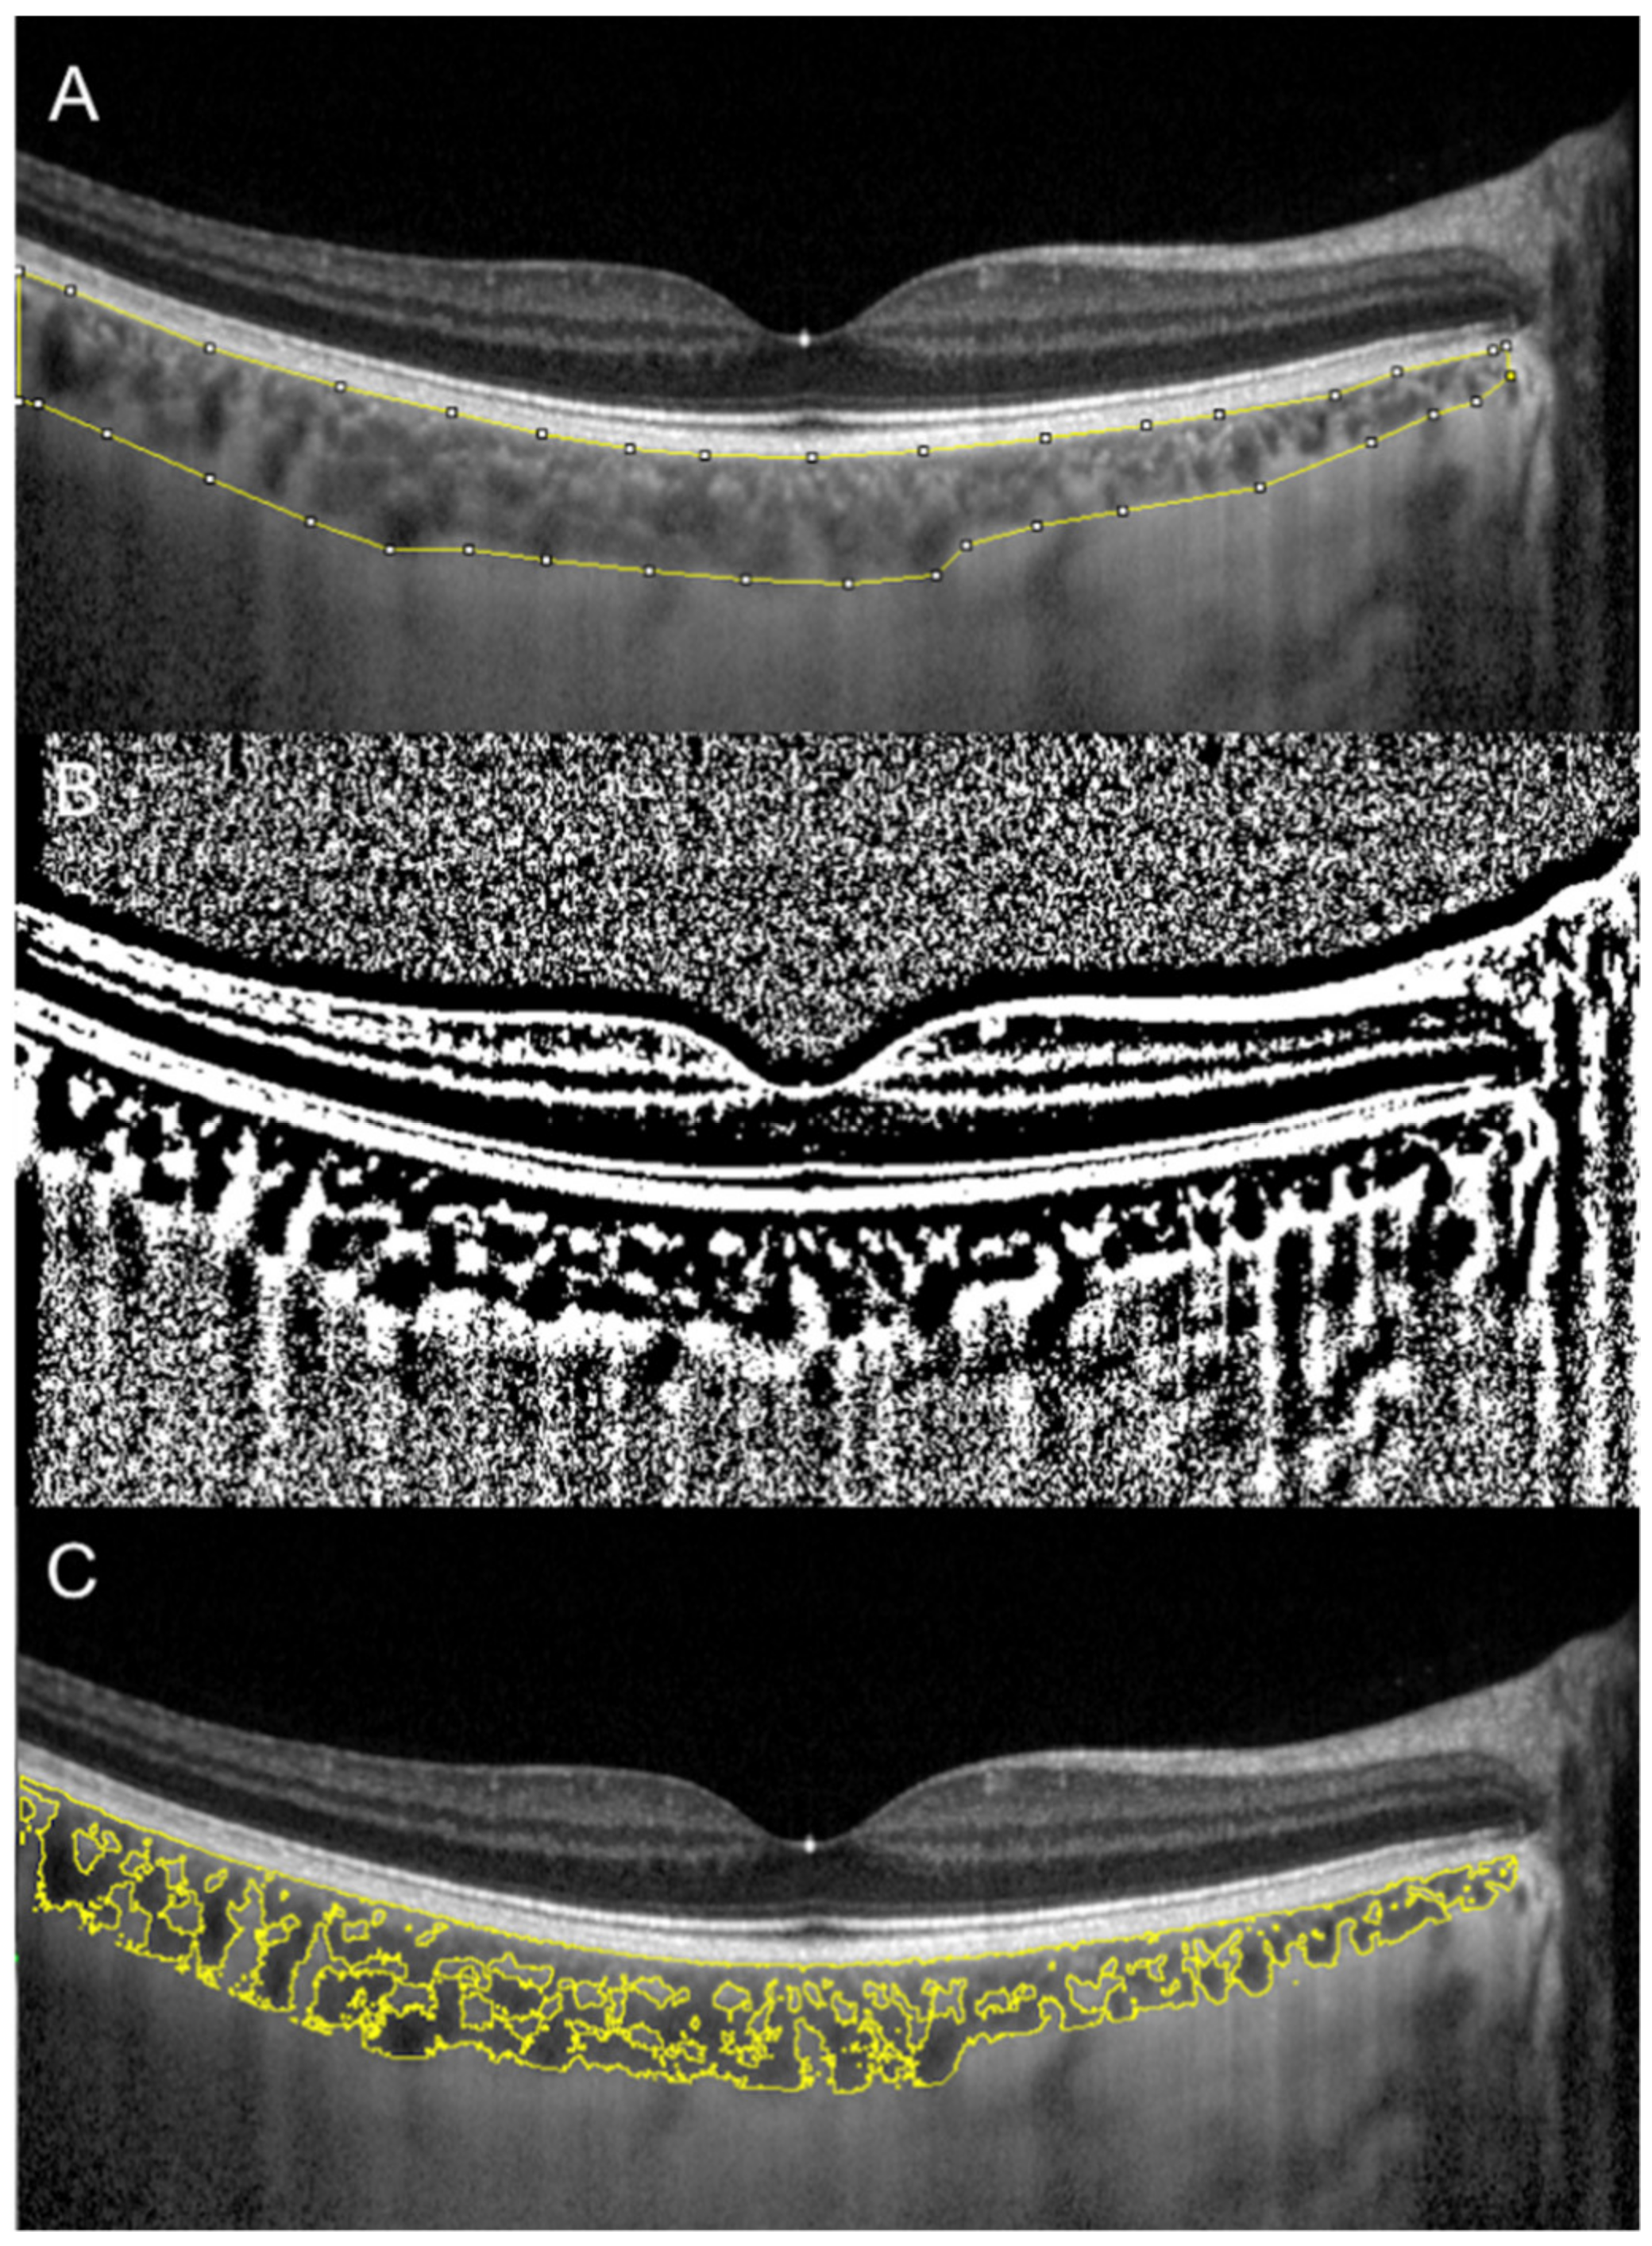

Sonoda et al. firstly described a technique to evaluate subfoveal LCA and SCA by an image binarization process of the EDI spectral domain (SD)-OCT foveal scan using the free software ImageJ (National Institutes of Health, Bethesda, MD, USA) [7,11]. Briefly, the OCT image is opened in ImageJ, and the polygon tool is used to select a region of interest of 1500 µm wide, centered on the fovea. The upper boundary of the region of interest is traced along the choroidal–RPE junction and the lower boundary along the sclerochoroidal junction to identify the total choroidal area (TCA). Image brightness is adjusted on the base of the average value obtained from the LCA of three choroidal vessels selected using the oval selection tool. After conversion to an 8-bit image, Niblack’s autolocal threshold is applied to binarize the image and to demarcate the LCA and the SCA. The image is converted to a red, green and blue image, and the color threshold tool is used to select the dark pixels, representing the LCA. The TCA and LCA are finally measured (Figure 1). The SCA is then obtained by subtracting LCA from TCA. The ratio between LCA and TCA is calculated.

Figure 1.

Choroidal vascularity index (CVI) calculation with binarization of enhanced-depth imaging (EDI) spectral domain optical coherence tomography (SD-OCT) image. Choroidal boundaries were traced to identify the total choroidal area (yellow lines) (A). The image was binarized using Niblack’s auto-local threshold (B). The color threshold tool was used to select the dark pixels, representing the luminal area (yellow lines) (C). The CVI is calculated dividing luminal area by total choroidal area.